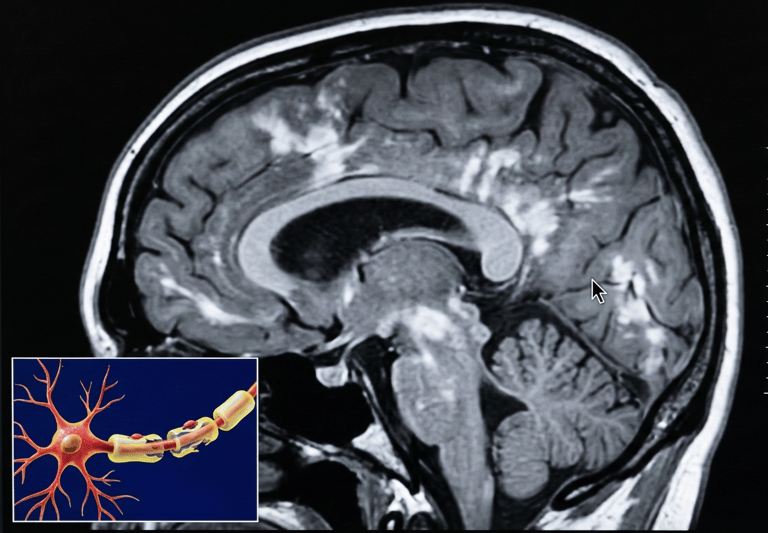

La esclerosis múltiple (EM) es una enfermedad del sistema nervioso central (cerebro, médula espinal y nervios ópticos) en la que participan procesos inmunológicos e inflamatorios que pueden afectar la mielina (cubierta protectora de las fibras nerviosas) y, en algunos casos, el propio tejido nervioso. Esto puede interferir con la transmisión de señales y manifestarse con síntomas neurológicos variables.

Resonancia magnética (MRI) para identificar lesiones compatibles en el sistema nervioso central.

Un curso rápidamente evolutivo y severo, definido (en documentación regulatoria europea) por 2 o más brotes incapacitantes en un año y evidencia de actividad en MRI (p. ej., lesiones con realce con gadolinio o aumento relevante de carga de lesiones).

MRI de seguimiento según criterio clínico.